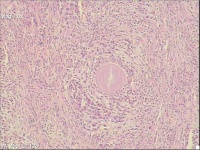

性别

男

年龄

56岁

前列腺增生

前列腺turp切除

灰白条状组织1堆,大小5x4x2cm。

前列腺增生腺管腔有这种形态很常见。

有些不在腺管里,感觉像钙化。

考虑符合:慢性前列腺炎伴腺体增生及淀粉小体形成。